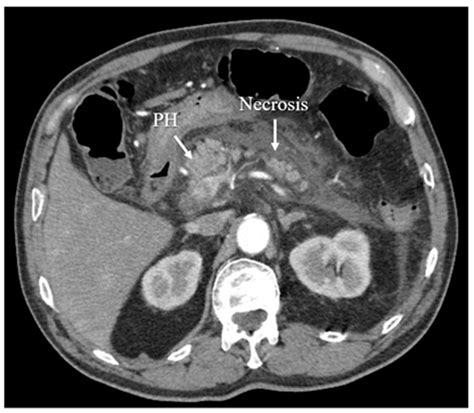

• Imaging Studies: Computed tomography (CT) scans and magnetic resonance imaging (MRI) are used to visualize the pancreas and detect necrosis.